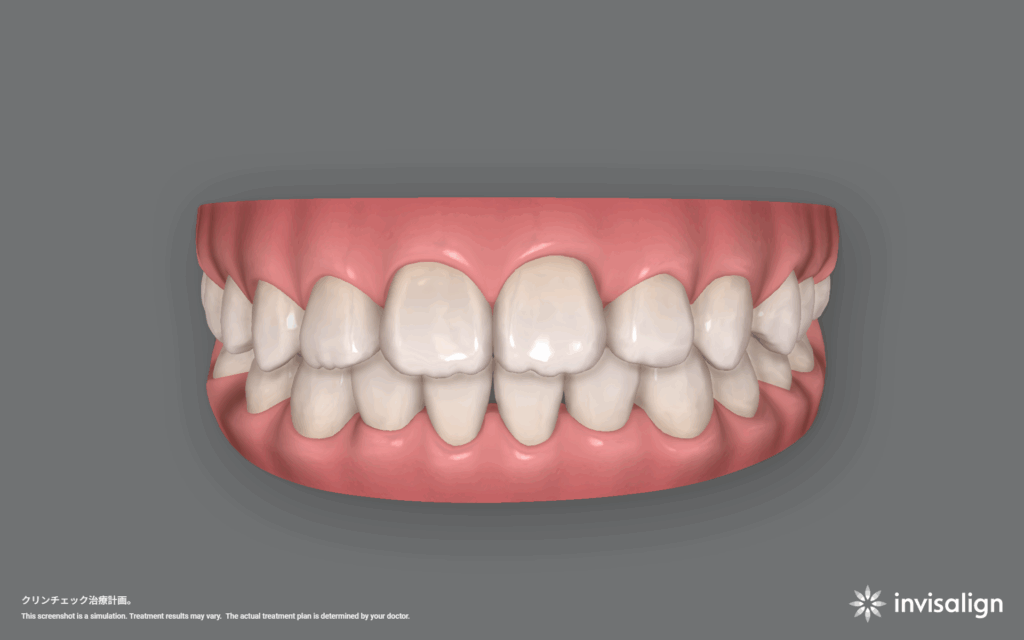

インビザライン矯正治療。57ステージ。治療費766,700円+調整料(初回)16,500円+調整料5,500円×回数+リテーナー55,000円。

1日20時間以上装着、1ステージ10日間。つまり570日、約19ヶ月、約1年7ヶ月の計画です。

今回の計画は、数段階に分けて治療をしていきます。1段階目は歯の位置関係をできるだけ整える。2段階目は先天欠損している部位の隙間をなくす。3段階目は全体的にはの位置を整える。ことにしました。結構時間がかかると思いますが、本人もお母さんも同意してくれたので治療を開始することになりました。